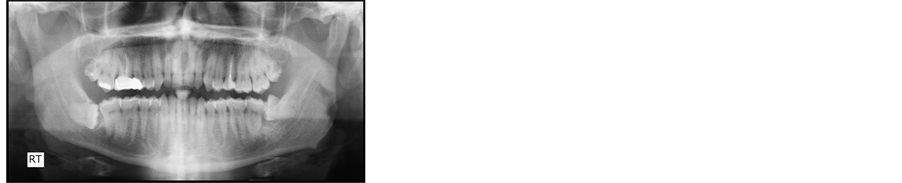

Panoramic radiograph indicated mandibular left third molar, which was impacted in the mandible, in horizontal position, with fused roots and near the mandibular canal (Figure 6).

Figure 6. Panoramic radiograph.